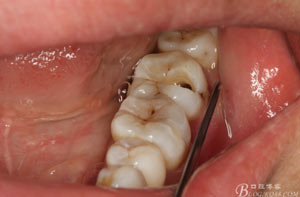

圖2.37牙冠基本完好,松動(dòng)Ⅰ度。合面有一開(kāi)髓孔被棉球覆蓋,頰側(cè)牙齦輕度紅腫。

圖3.取出棉球口內(nèi)發(fā)現(xiàn)37合面有開(kāi)髓孔,探針出血,頰側(cè)牙齦紅腫